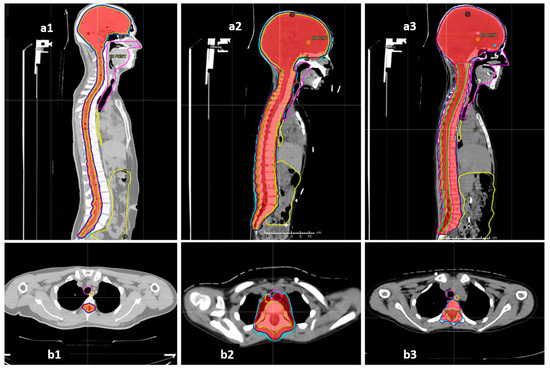

The COG-SIOPE guidelines recommend the inclusion of vertebral bodies into the CSI target in skeletally immature children to prevent skeletal abnormalities arising from mismatched growth between the segments of the partially irradiated vertebra. The initial few CSI plans were generated strictly adhering to this; however, after one of them developed severe Grade 3 mucositis, we discussed and noticed that these plans either entailed high dose delivery to the immediately anterior OARs up to 100% of the prescription dose, or sharp, irregular underdosing of the target volume. Thereafter, we adopted a modified novel approach to planning in these pre-pubertal patients to mitigate these concerns. The final spinal target contours concordant with the SIOPE guidelines included the vertebral body (PTV_spine), but the spinal canal with roots with circumferential margin was also separately specified as the target (PTV_canal), which required stricter coverage with the prescription dose. The prescription and target coverage requirements before planning mandated proper coverage of the PTV_canal while routinely prescribing a uniform low dose to the anterior part of the PTV_spine at the vertebral bodies adjacent to the midline mucosal and visceral structures including the pharyngeal constrictors, oesophagus, and heart. The plan was generated keeping these aspects of differential target coverage as part of the optimisation parameters, and during plan evaluation, we verified the vertebral body coverage and independently robustly assessed the PTV_canal coverage accounting for both translational shifts and range uncertainties. This novel approach allowed us to spare the immediately anterior OARs much better while ensuring no or minimal underdosing in the actual target volume at risk as well as no sharp dose gradient within the vertebral body. Representative dose colour wash images of the plans illustrating this further are shown in Figure 4.

Figure 4.

Representative sagittal and axial sections showing the dose colour wash 98% (red) and 95% (cyan) for target coverage and anterior mucosal structures (oesophagus—yellow, midline mucosa—magenta, bowel bag—yellow): (a1,b1) vertebral-sparing CSI (VS-CSI) plan for skeletally mature patients. The spinal target canal includes the spinal canal and exiting nerve roots with 5 mm margin. Anterior structures are spared well. (a2,b2) Traditional vertebral-inclusive CSI (VI-CSI) plan for skeletally immature patients (children). The target includes the spinal canal, exiting nerve roots, and entire vertebral body with 5 mm margin. The axial section shows significant spillage of prescription doses into the anterior mucosal structures. (a3,b3) Modified vertebral-inclusive CSI (VI-CSI) plan for skeletally immature patients (children). The target includes the spinal canal, exiting nerve roots, with 5 mm margin, and the entire vertebral body without any additional PTV margin. The axial section shows adequate and homogenous coverage of the vertebral body between 95–98% isodose, while the anterior mucosal structures are spared well.

The dosimetric benefits of proton therapy and the superior OAR sparing do seem to translate to practical benefits; acute toxicities during proton therapy were mostly limited to alopecia, mild dermatitis, and mild mucositis. All our patients had dermatitis, but limited to Grades 1 and 2. The incidence of dermatitis after proton CSI in the available literature has been found to range from 86 to 100% and is not significantly different between protons and photons [29,30,31]. However, there is a definite reported improvement in the incidence and severity of Grade 2 and above mucositis and GI toxicity, with Brown et al. reporting a relative incidence of 26% vs. 71%, p = 0.004 between proton CSI and photon CSI [30]. We found a further lower incidence of clinically symptomatic mucositis in our patient cohort where the majority (60%) of our patients had no mucositis or Grade 1 mucositis (27.5%). Only 5% suffered Grade 2 mucositis, and a solitary incidence of Grade 3 mucositis was seen solely in one of the earliest treated children, which was prevented thereafter by the modified approach to VI-CSI planning as described previously and demonstrated in Figure 4(a3,b3) vs. Figure 4(a2,b2). The relative supremacy of IMPT by pencil-beam scanning over passive scattering technology as well as the in-house modifications in target definition and planning as described earlier perhaps explain the further reduced mucositis and GI toxicities in our patients. The haematological toxicities too were only seen to be Grade 3 when in conjunction with an intensive daily Carboplatin chemotherapy regimen. Previous studies also have reported a significant reduction in haematological toxicities after proton CSI rather than photon CSI [32].